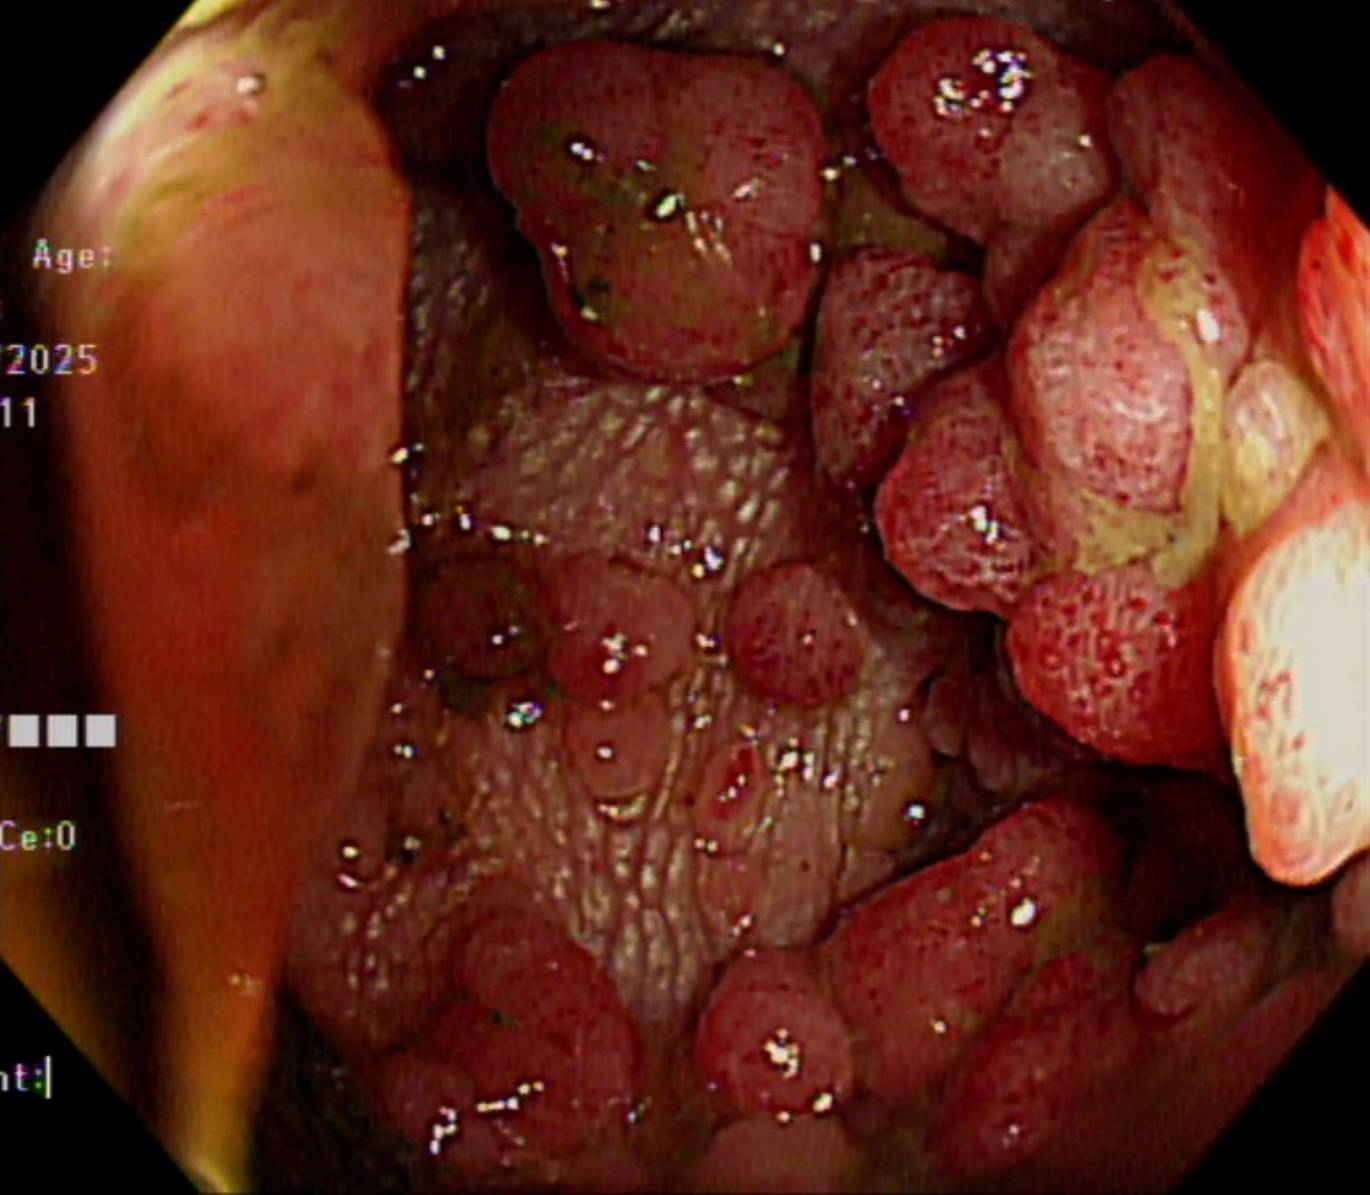

嘉義基督教醫院提醒罕見家族性腺瘤性瘜肉症於腸道長滿瘜肉不可輕忽。(圖/嘉義基督教醫院提供)

(記者任芳葵嘉義報導)家族性腺瘤性瘜肉症(Familial Adenomatous Polyposis,簡稱FAP)是一種少見的遺傳疾病,嘉義基督教醫院提醒對健康的威脅卻不容忽視,若不及早診斷並接受適當治療,幾乎百分之百會發展成為大腸直腸癌。

嘉義基督教醫院大腸直腸科主任朱峻廷醫師表示,FAP是顯性遺傳疾病,只要父母其中一方帶有突變基因,下一代就有50%的機率會遺傳到。根據統計,FAP患者通常在青少年時期就開始出現大腸瘜肉,到了30歲左右,腸道可能布滿上百、上千顆瘜肉,若未治療,90%以上會在中年以前癌化,「只要活得夠久,終其一生幾乎百分之百會演變成大腸癌」。這也是為什麼醫界會不斷強調,一旦家族中有人年輕時就罹患大腸癌或出現大量瘜肉,其他成員必須提高警覺。